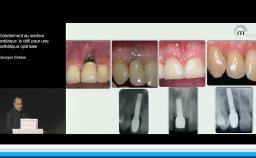

Tous les types d’implants peuvent être utilisés en secteur antérieur, mais l’utilisation de connexions au niveau osseux offre plus de latitude sur le placement de l’implant et sur la réhabilitation prothétique. Afin de limiter les proximités entre implants et entre dents et implants, l’utilisation d’implants de faible diamètre et la réduction du nombre d’implants sont des options à considérer.

- de choisir le type et le nombre d’implants à placer en secteur antérieur pour optimiser le résultat esthétique